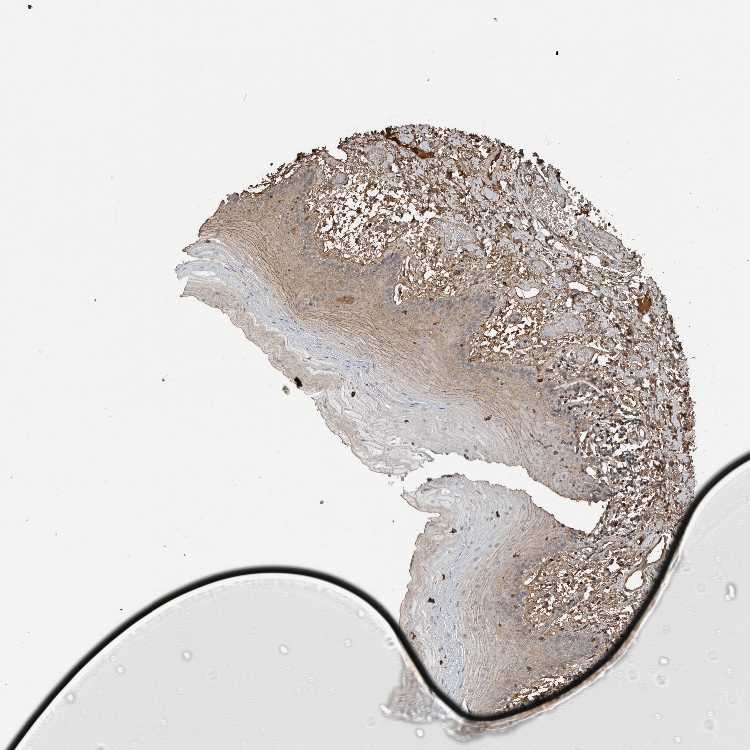

ORAL MUCOSA - Antibody stainingi

Antibody staining in the annotated cell types in the current human tissue is reported as not detected, low, medium, or high, based on conventional immunohistochemistry profiling in selected tissues. This score is based on the combination of the staining intensity and fraction of stained cells.

Each image is clickable and will lead to virtual microscopy that enables deeper exploration of all samples and also displays staining intensity scores, fraction scores and subcellular localization as well as patient and tissue information for each sample.

Antibody HPA025815

Squamous epithelial cells Medium